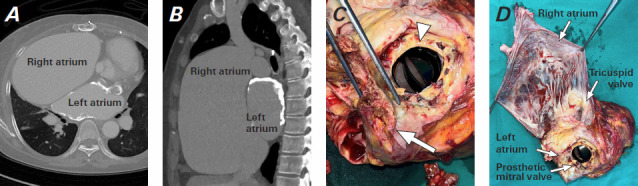

A 62-year-old woman who had undergone mitral valve replacement 24 years ago was admitted to the hospital with congestive heart failure. She needed heart transplantation for stage D heart failure. Preoperative cardiac computed tomographic scans showed a severely calcified left atrium and a large right atrium. Given that the left atrium's calcification was too severe to suture, the calcified left atrial wall was broadly resected, and the resected left atrial wall was reconstructed with a bovine pericardial patch for anastomosis with the donor's left atrial wall. The operation was completed without heavy bleeding, and the patient was discharged from the hospital with no complications.